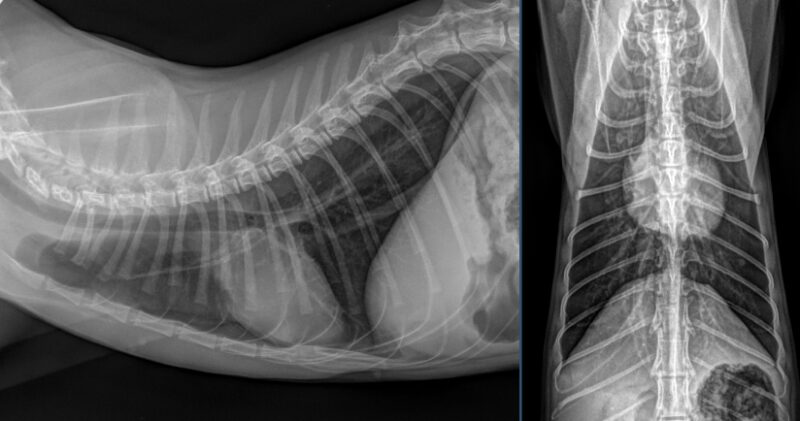

Besten Dank für die Übermittlung dieses spannenden Falles! Es liegen Röntgenbilder des Thorax und des Abdomens in 2 Ebenen vor (sinistro-dextraler Strahlengang, sowie ventro-dorsaler Strahlengang). Wesentliche Hauptbefunde sind im Bereich des muskuloskelettalen Systems, als auch im Abdomen zu vermerken.

Trachea/Ösophagus, Mediastinum, Pulmonalgefäße, Aorta/V.cava, Pleuralraum, sowie alle abgebildeten ossären Strukturen stellen sich unauffällig dar. Die Herzsilhouhette misst im VHS 7,5 Wirbelkörper. Das Thoraxröntgen stellt sich somit unauffällig dar, ohne Hinweis auf Rippenfrakturen, Pneumothorax oder Lungenkontusionen.